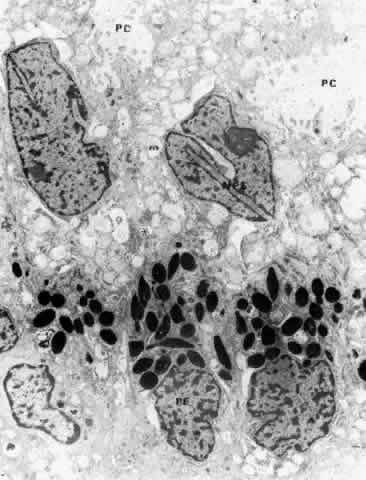

CILIARY BODY STROMA

The stroma of the ciliary body contains all the usual components of extracellular matrix including collagens, elastic system fibers, and small matrix molecules such as proteoglycans. The cellular components are melanocytes, fibroblasts, blood vessels, and nerves, besides the large quantity of smooth muscle comprising the bulk of this tissue. In the first one and one-half decades the nonvascular connective tissue in the ciliary processes is scanty, resulting in the thin, underdeveloped appearance of the juvenile ciliary processes (Fig. 28A). Their vessels are primarily fenestrated capillaries and veins, forming plexi (see later section on blood supply). The subepithelial tissue in the processes and plicae becomes very much thickened by collagenous and hyaline material with aging (Fig. 28B and C), extending down to the ciliary muscle itself. In the deeper stroma, capillaries are usually not fenestrated and show intermittent pericytes outside the endothelial cell layer, surrounded by basement membrane that merges with that of the endothelial cells (Fig. 29). The ciliary processes are essentially vascular structures and do not contain extensions of the ciliary muscle, so the muscle has the same thickness under the processes as under the ciliary valleys (Fig. 30).

Fig. 29. Intermittent pericyte (P) coverage and lack of fenestrae in the endothelial cell wall characterize capillaries of the deeper stroma in the pars plicata. Basement membrane (BM) is multilayered. Fibroblast (FB) has active rough endoplasmic reticulum and a large cisterna with granular material. A small clump of elastic system microfibrils is seen at its upper edge (arrow). (X 20,900)